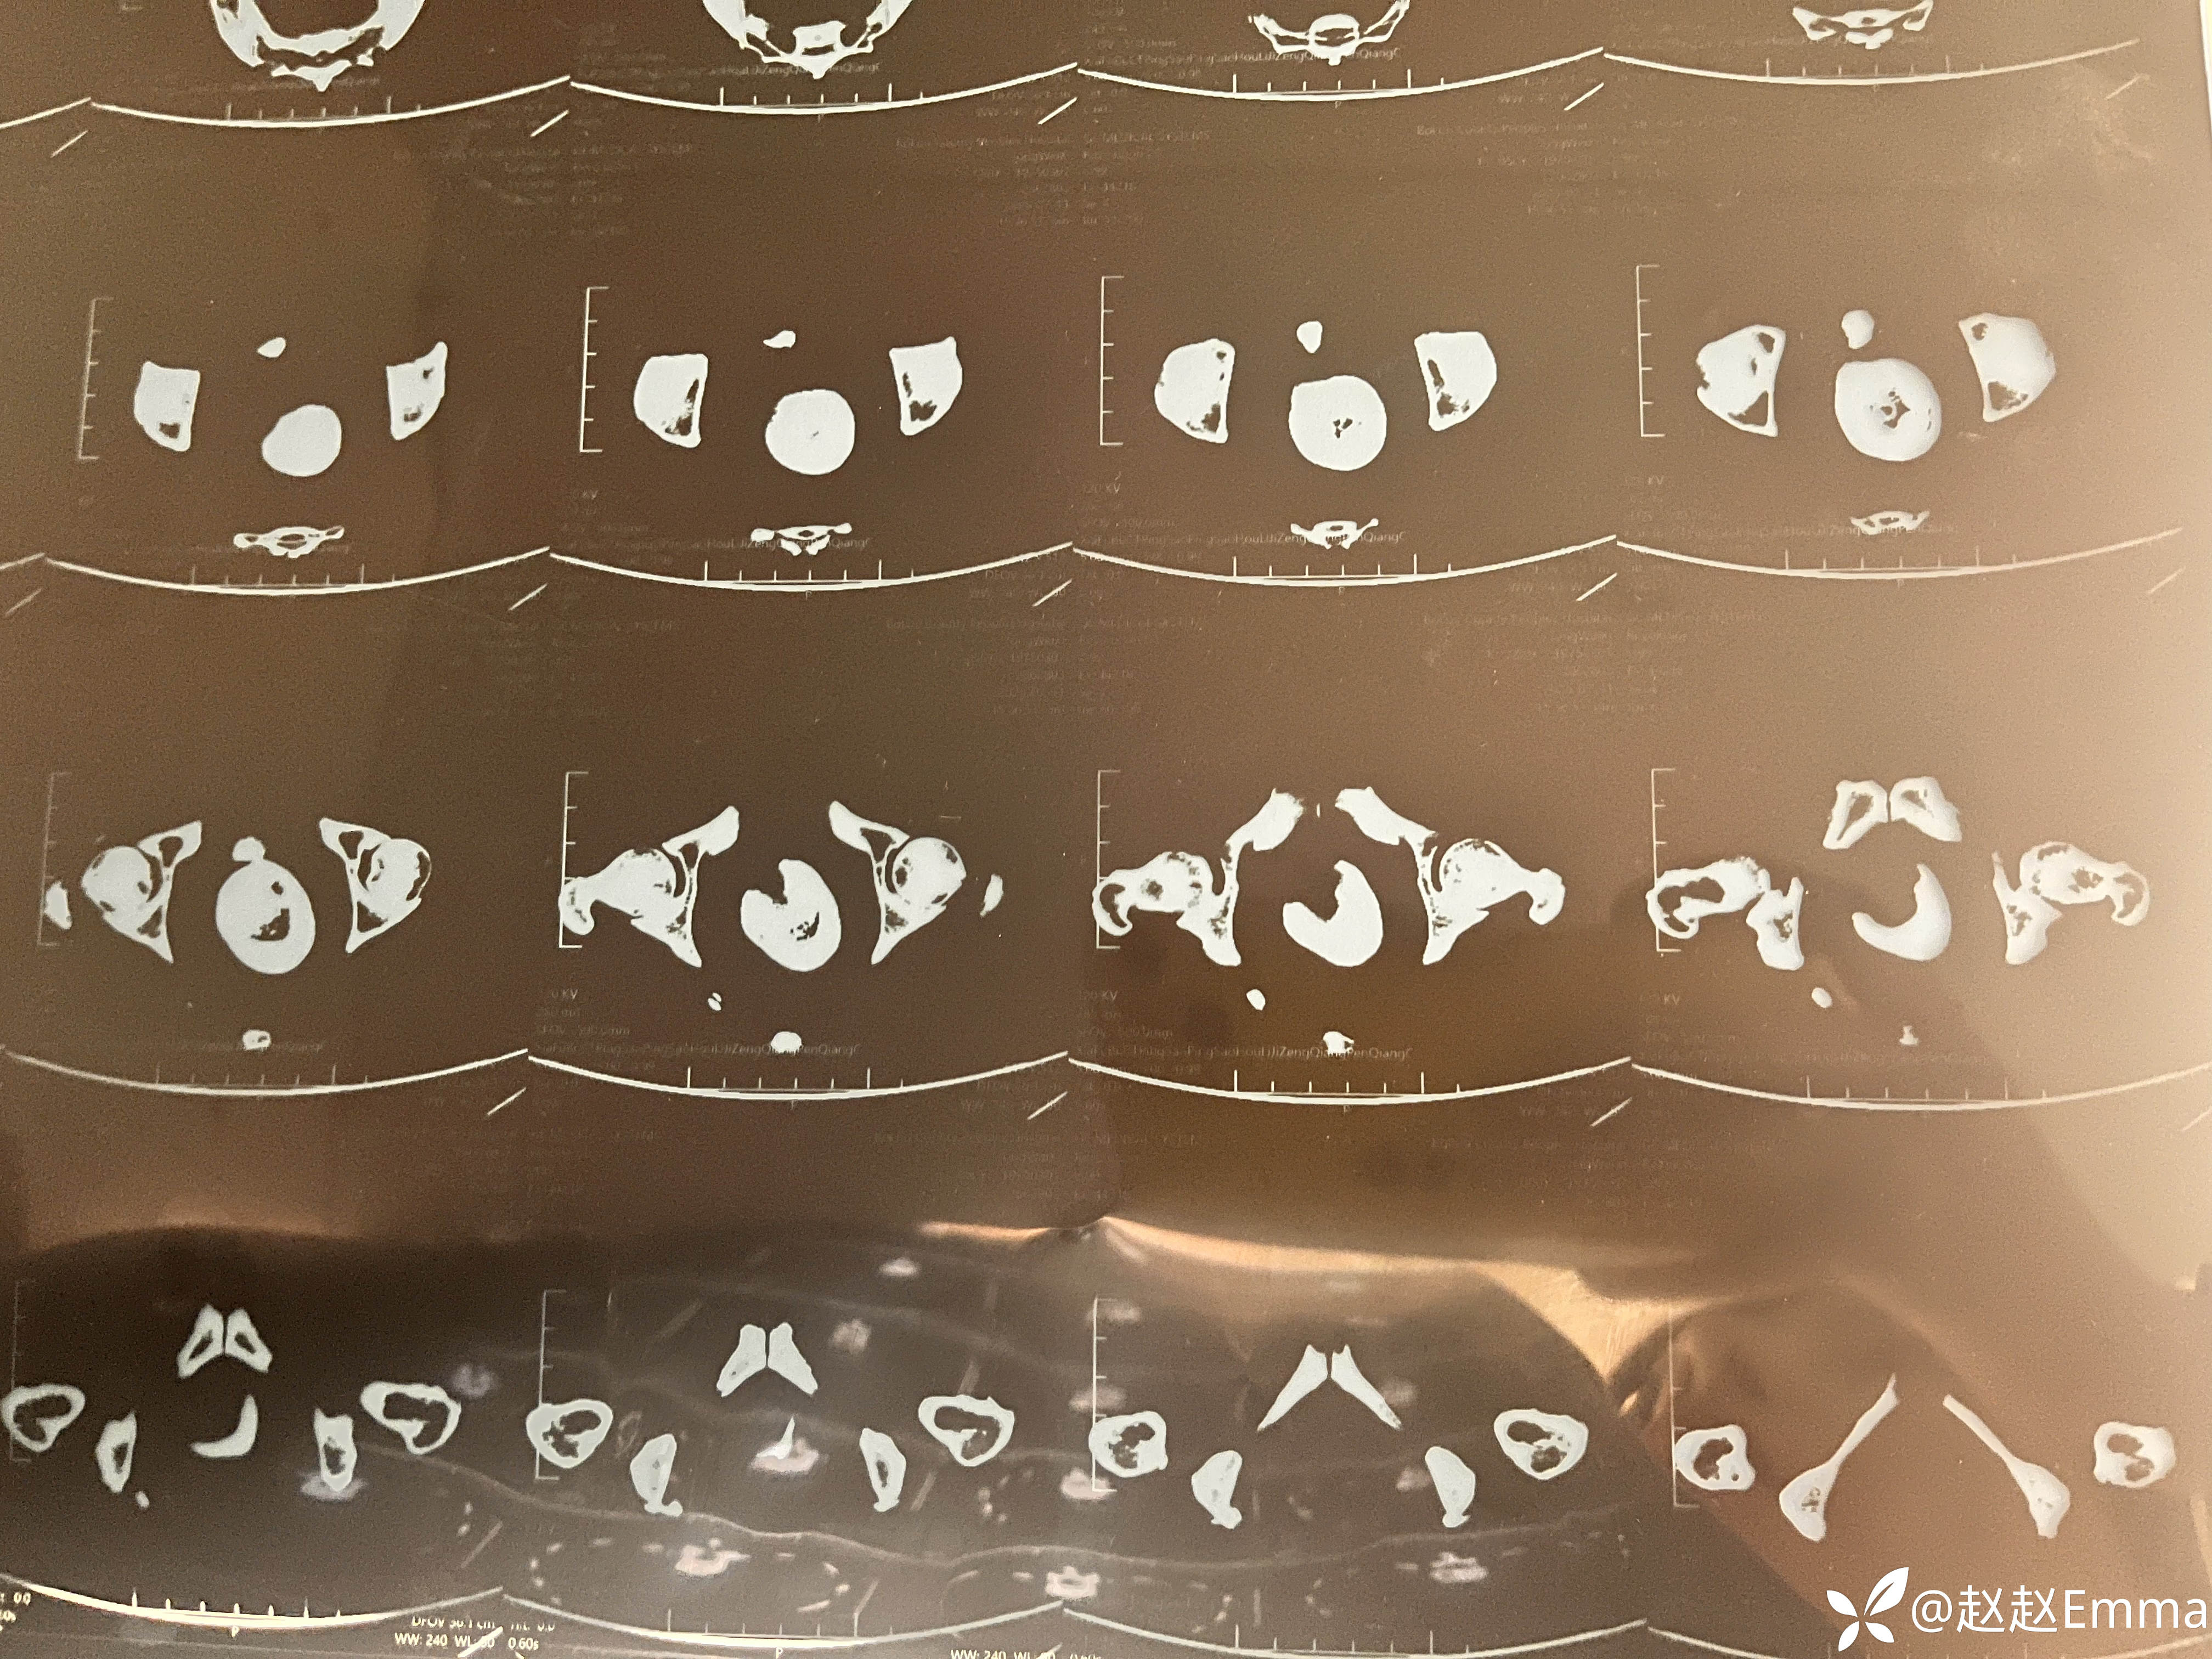

辅助检查:下腹部+盆腔CT:右肾较小,实质密度不均,可见稍低密度影,边界欠清;肾盂肾盏似有扩大;左肾形态、大小正常,皮髓质分界清楚,肾实质内未见异常密度影。左侧肾盂肾盏扩张积液,内见少许高密度影。左侧输尿管扩张;右侧输尿管形态正常,未见扩张或狭窄。膀胱充盈一般,壁欠光整,膀胱腔内见高密度影及少量含气影。子宫不大,宫腔增宽,内见液平及含气影,子宫下段-阴道见不规则高密度影,该高密度影与膀胱内高密度影似相连。盆腔内未见明显肿大淋巴结。影像诊断:1.子宫下段-阴道、膀胱内可见高密度影,结合病史,考虑异物存留可能,高密度影似相连,提示膀胱-阴道瘘可能;膀胱腔内积气,子宫腔内积液、积气,考虑合并感染。2.左肾结石并积水,左侧输尿管扩张、积液;右肾萎缩,右肾可疑积液,肾实质密度不均。